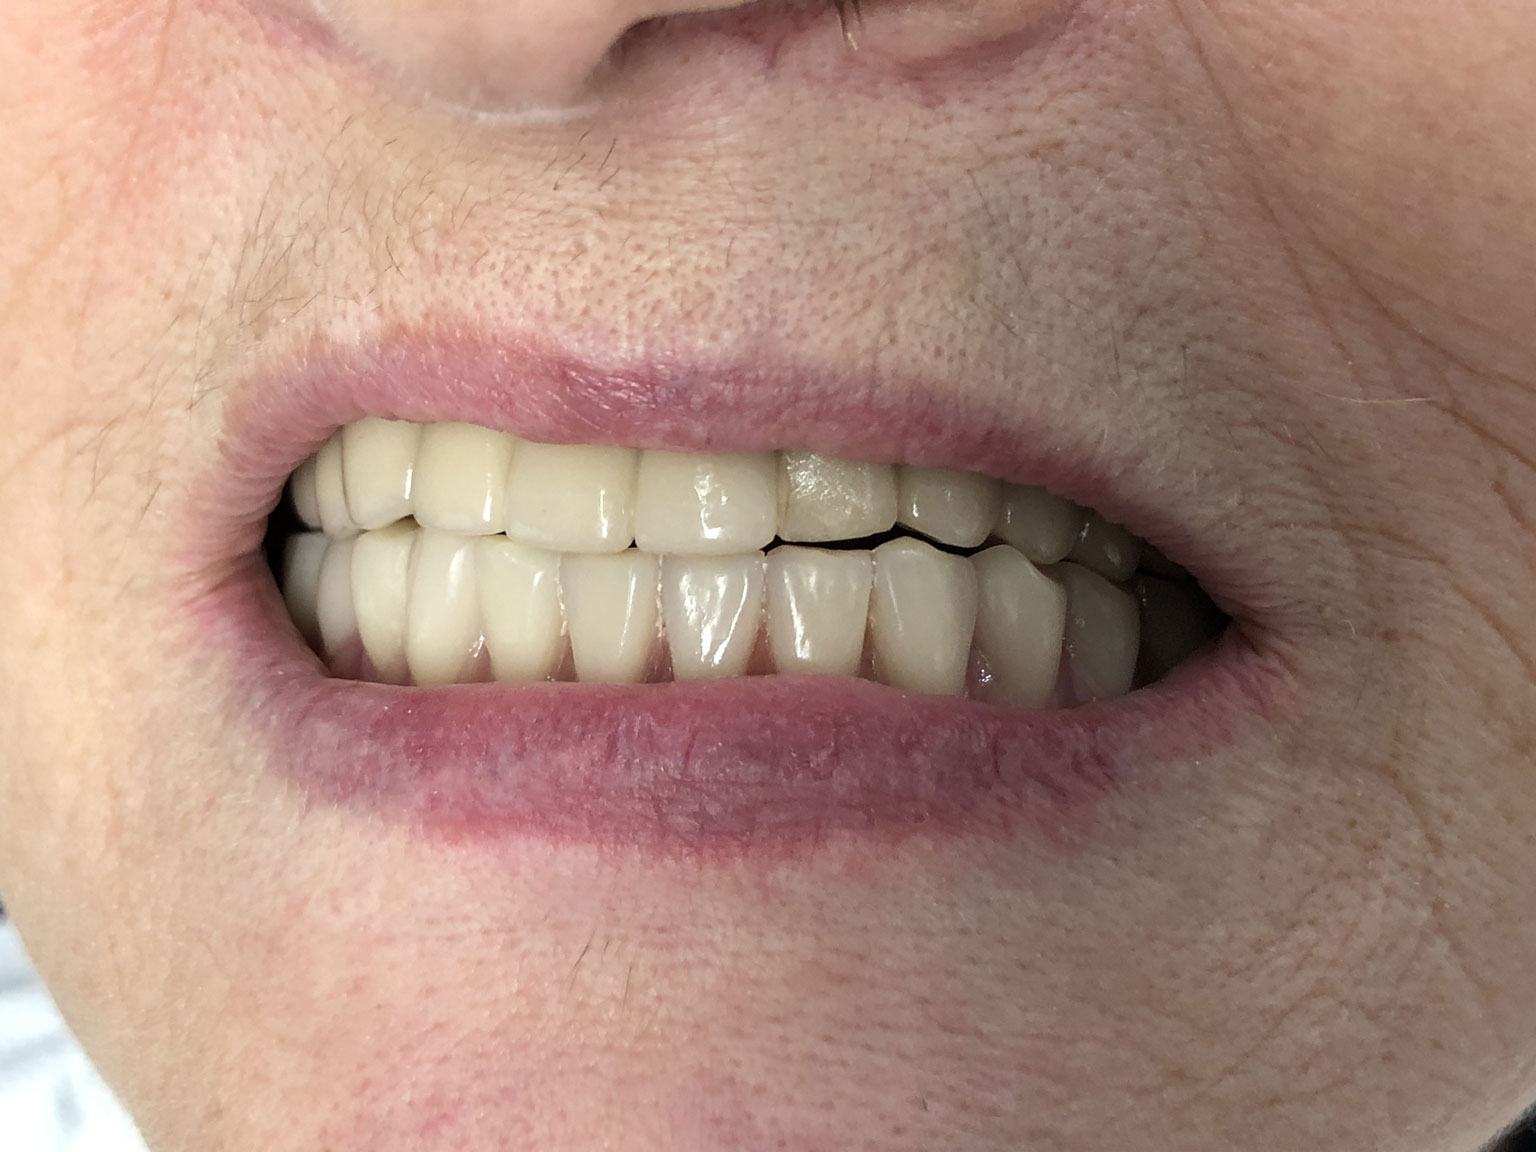

Arcata completa in Zirconio